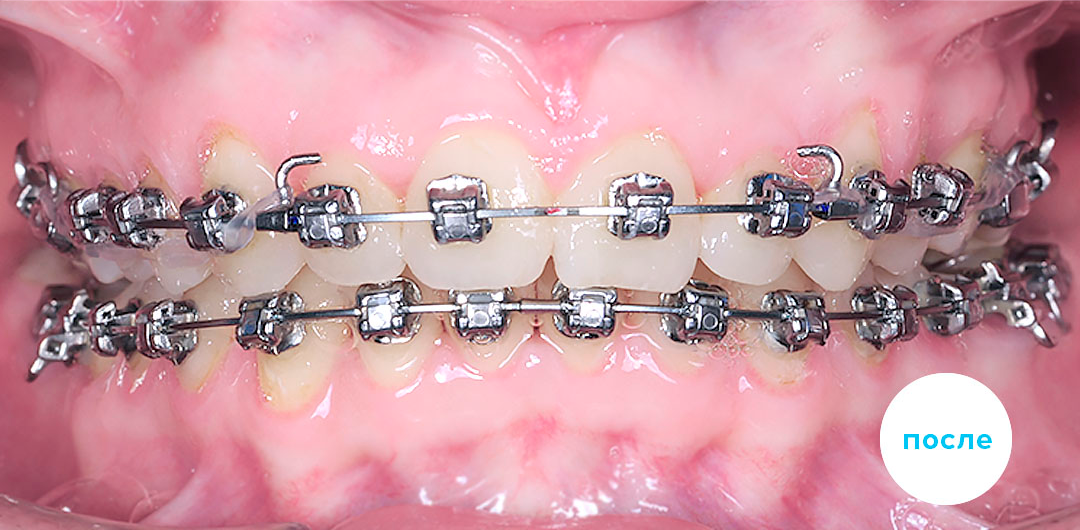

Работы специалиста